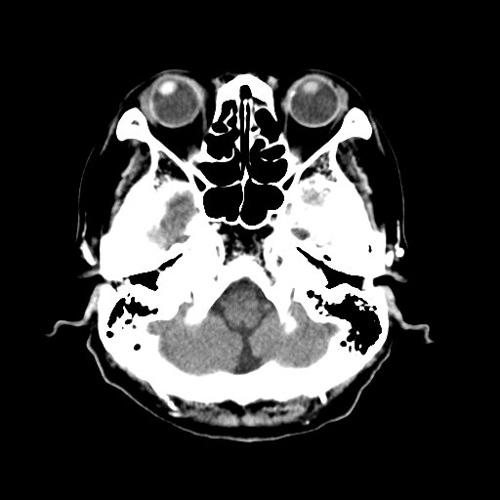

【CT(computed tomography)】

管球(ドーナツ状の部分にあるX線を出す機械)がX線を出しながら体の周りを回転し、人体を透過したX線をコンピューター処理して画像化します。短時間で広い範囲を撮影でき、様々な方向からの画像や3Dを作成します。